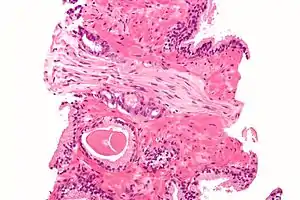

A diagnosis of prostate cancer requires a biopsy of the prostate. Prostate biopsies are typically taken by a needle passing through the rectum or perineum, guided by transrectal ultrasound imaging, magnetic resonance imaging (MRI), or a combination of the two.[22][20] Ten to twelve samples are taken from several regions of the prostate to improve the chances of finding any tumors.[20] Biopsies are examined under a microscope by a pathologist, who determines the type and extent of cancerous cells present. Cancers are first classified based on their appearance under a microscope. Over 95% of prostate cancers are classified as adenocarcinomas (resembling gland tissue), with the rest largely squamous-cell carcinoma (resembling squamous cells, a type of epithelial cell) and transitional cell carcinoma (resembling transitional cells).[23]

Next tumor samples are graded based on how much the tumor tissue differs from normal prostate tissue; the more different the tumor appears, the faster the tumor is likely to grow. The Gleason grading system is commonly used, where the pathologist assigns a number from 1 (similar to prostate tissue) to 5 (least similar) for the most common pattern observed under the microscope, then does the same for the second-most common pattern. The sum of these two numbers is the Gleason score.[23] The total scores of 2 through 5 are no longer commonly used in practice, making the lowest score 6, and the highest score 10. Scores are commonly grouped into Gleason grade groups: a score of 6 or lower is Gleason grade group 1; a score of 7 with the first number (from the most common pattern) 3 and the second number 4 is grade group 2; the reverse – first number 4, second number 3 – is grade group 3; a score of 8 is grade group 4; a score of 9 or 10 is grade group 5.[23] Higher Gleason scores and higher grade groups represent cancer cases likely to be more aggressive with worse prognosis.[23]